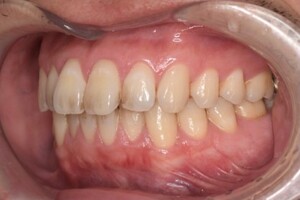

CASE 2

| 年齢・性別 | 30代・男性 |

|---|---|

| 主訴 | 歯石を取りたい |

| 治療内容 | 超音波スケーラーでの歯石除去 |

| 治療期間 | 60分 |

| 治療費 | 初診料を含め約4,500円 |

| リスク・副作用 | 歯ぐきに違和感や痛みを覚える場合がある。 1週間程度、歯を磨くといつもより出血することがある。 腫れていた歯ぐきが引き締まることで歯ぐきが下がった様に見える。 歯ぐきが下がることで歯がみしやすくなることがある。 一時的に歯の動揺(ゆれ)が増す場合がある。 |